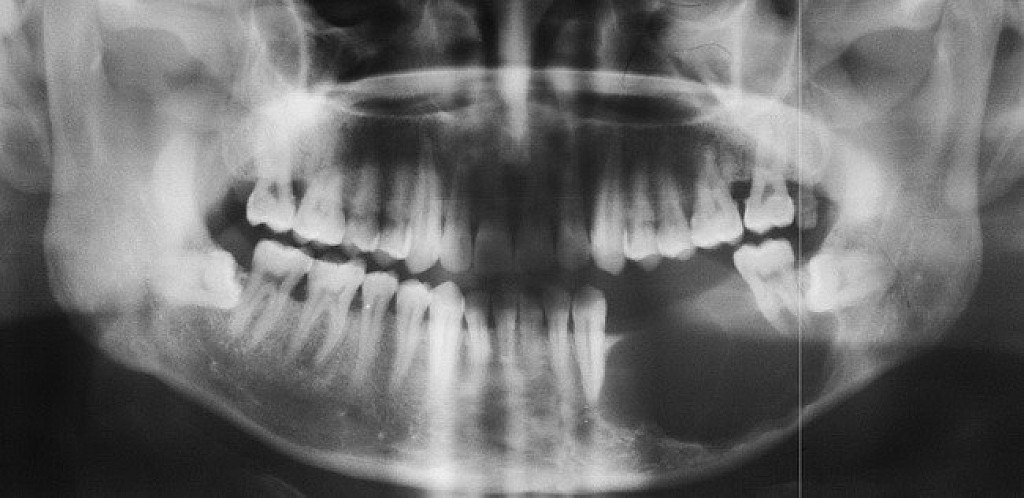

Ameloblastoma is a rare odontogenic tumor, which means it's formed from the normal tissues found in the mouth. Their location is predominately the lower jaw, also known as the mandible. Still, they can be found in the upper jaw or maxilla as well. Sometimes, ameloblastomas are located in the soft tissues surrounding the jaws. There is no known cause for this kind of tumor. However, it may be associated with impacted third molars. Ameloblastomas are usually noncancerous (benign), and they generally affect people between 40 and 60 years old.

Ameloblastoma is usually painless, with the only symptom being swelling in the area. It is usually only identified on radiographic examination in a dental office. Early developing lesions do not displace teeth or cause numbness, so the patient may not know a tumor is growing in one of their jawbones. If a potential lesion is identified on a dental radiograph, more elaborate imaging is required. This will include a CAT scan and possibly an MRI. However, the diagnosis cannot be solely determined by imaging. It requires a biopsy to make the final diagnosis. Cysts will sometimes appear similar to the ameloblastoma on the imaging.